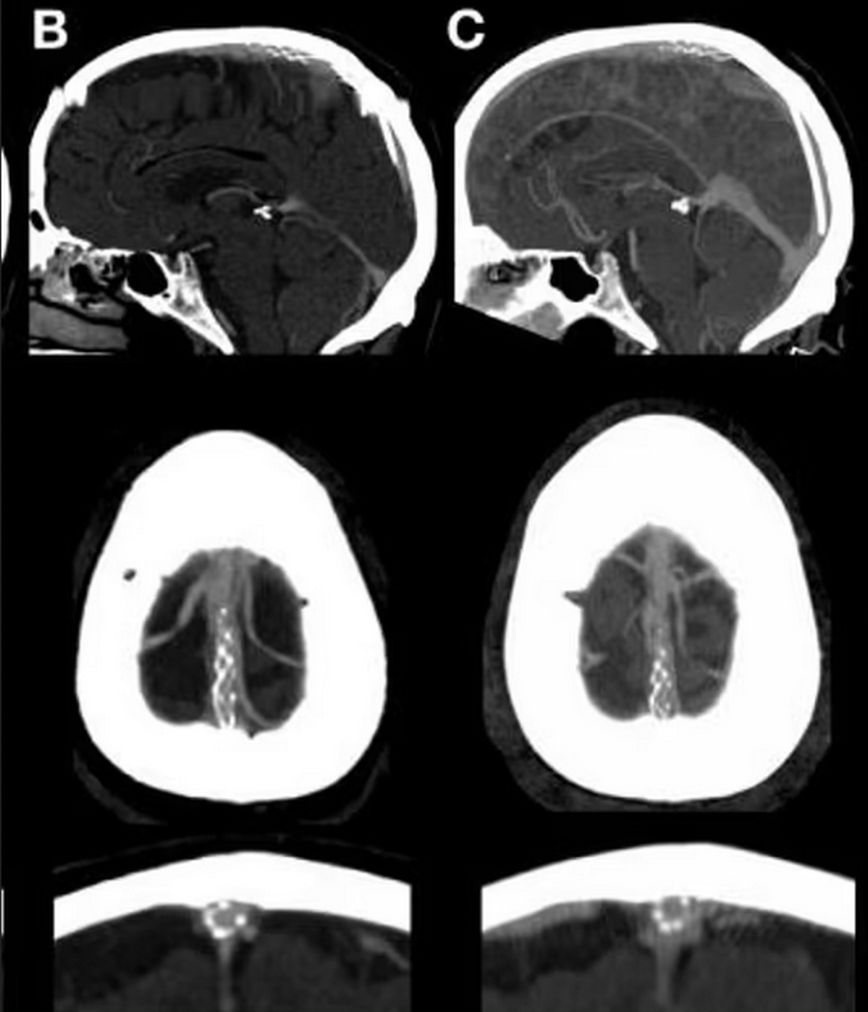

Η ομάδα χρησιμοποιεί τα αιμοφόρα αγγεία ως φυσικό δρόμο προς τον εγκέφαλο, τα οποία είναι εφοδιασμένα με αισθητήρες που καταγράφουν τη δραστηριότητα.

Αυτά τα σήματα αποστέλλονται στη συνέχεια μέσω μιας μονάδας τηλεμετρίας σε έναν μικρό υπολογιστή που είναι κολλημένος με ταινία στο στήθος του ασθενούς, ο οποίος ερμηνεύει ποιες ενέργειες θέλει να κάνει το άτομο στον κοντινό υπολογιστή, όπως αποστολή μηνυμάτων, email και αγορές μέσω Διαδικτύου.

Η συσκευή Stentrode μήκους 40 χιλιοστών είναι μικρή και ευέλικτη, επιτρέποντάς της να περνά με ασφάλεια μέσα από καμπυλωτά αιμοφόρα αγγεία στον εγκέφαλο.

Η ομάδα σημειώνει ότι η διαδικασία είναι παρόμοια με αυτή ενός βηματοδότη και δεν απαιτεί ανοιχτή εγχείρηση εγκεφάλου.

Μόλις εμφυτευθεί το τσιπ, οι αισθητήρες τοποθετούνται μέσα από τα αγγεία και εισάγονται σε μια εσωτερική μονάδα τηλεμετρίας που συνδέεται με έναν ασύρματο πομπό κολλημένο με ταινία στο στήθος του ασθενούς.

Η εγκεφαλική δραστηριότητα συλλέγεται από τους αισθητήρες, και αποστέλλεται στον πομπό που τους ερμηνεύει σε εργασίες στον υπολογιστή. Το σύστημα περιλαμβάνει επίσης ένα eye-tracker για την πλοήγηση του δρομέα στην οθόνη του υπολογιστή.